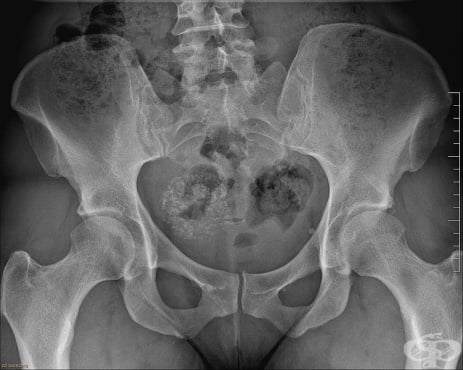

Лейомиомата се диагностицира чрез тазов преглед и ултразвуково изследване.

Основно значение за поставянето на диагнозата миома имат клиничната картина и образните изследвания, предимно ехографията.

Поставянето на диагнозата миома обикновено не е трудно, но понякога могат да съществуват и затруднения. Основно значение се отдава на огледа и палпацията, образните изследвания, параклинични изследвания, сондирането на матката и други. Посредством тези методи може нерядко да се определи размерът, б...

Миома Матка с миоми Видове миома Симптоми при миома Гинекологичен преглед Ехография на миома Хистероскопия Хистерография Хирургично лечение на миома Аблация на ендометриума